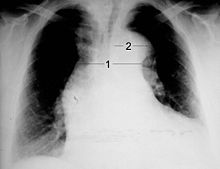

Chest X-ray

Aortic dissection on CXR: Note is made of a wide aortic knob.

Chest radiography may demonstrate a change in the morphology of the thoracic aorta which can be seen in aortic dissection. Classically, new widening of the mediastinum on radiograph is of moderate sensitivity for detecting an ascending aortic dissection; however, this finding is of low specificity, as many other conditions can cause apparent widening of the mediastinum.

There are several other associated radiographic findings:

• The "calcium sign" describes an apparent separation of the intimal calcification from the outer aortic margin by greater than 10 mm.

• Pleural effusions, more commonly in descending aortic dissections, and typically left sided.

• Other: obliteration of the aortic knob, depression of the left mainstem bronchus, loss of the paratracheal stripe, and tracheal deviation.

Importantly, about 12 to 20% of aortic dissections are not detectable by chest radiograph; therefore, a "normal" chest radiograph does not rule out aortic dissection. If there is high clinical suspicion, a more sensitive imaging test (CT angiogram, MR angiography, or transesophageal echo) may be warranted.